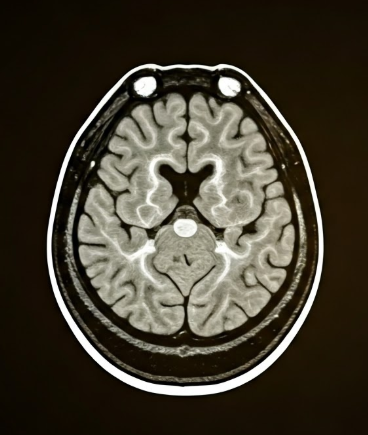

뇌졸중 위험 신호🧠

경동맥이 좁아지거나 플라크가 떨어져 나가면 뇌혈관을 막아 뇌경색을 유발할 수 있어요. 이때 일과성허혈발작(TIA)이라 불리는 일시적인 신경학적 이상이 먼저 나타납니다.

경동맥초음파는 이러한 전조 징후를 조기에 포착할 수 있어, 실제 뇌졸중으로 이어지기 전에 치료할 기회를 줍니다. 특히 혈압이 높거나 흡연을 많이 한 분, 가족력이 있다면 적극 권장돼요.